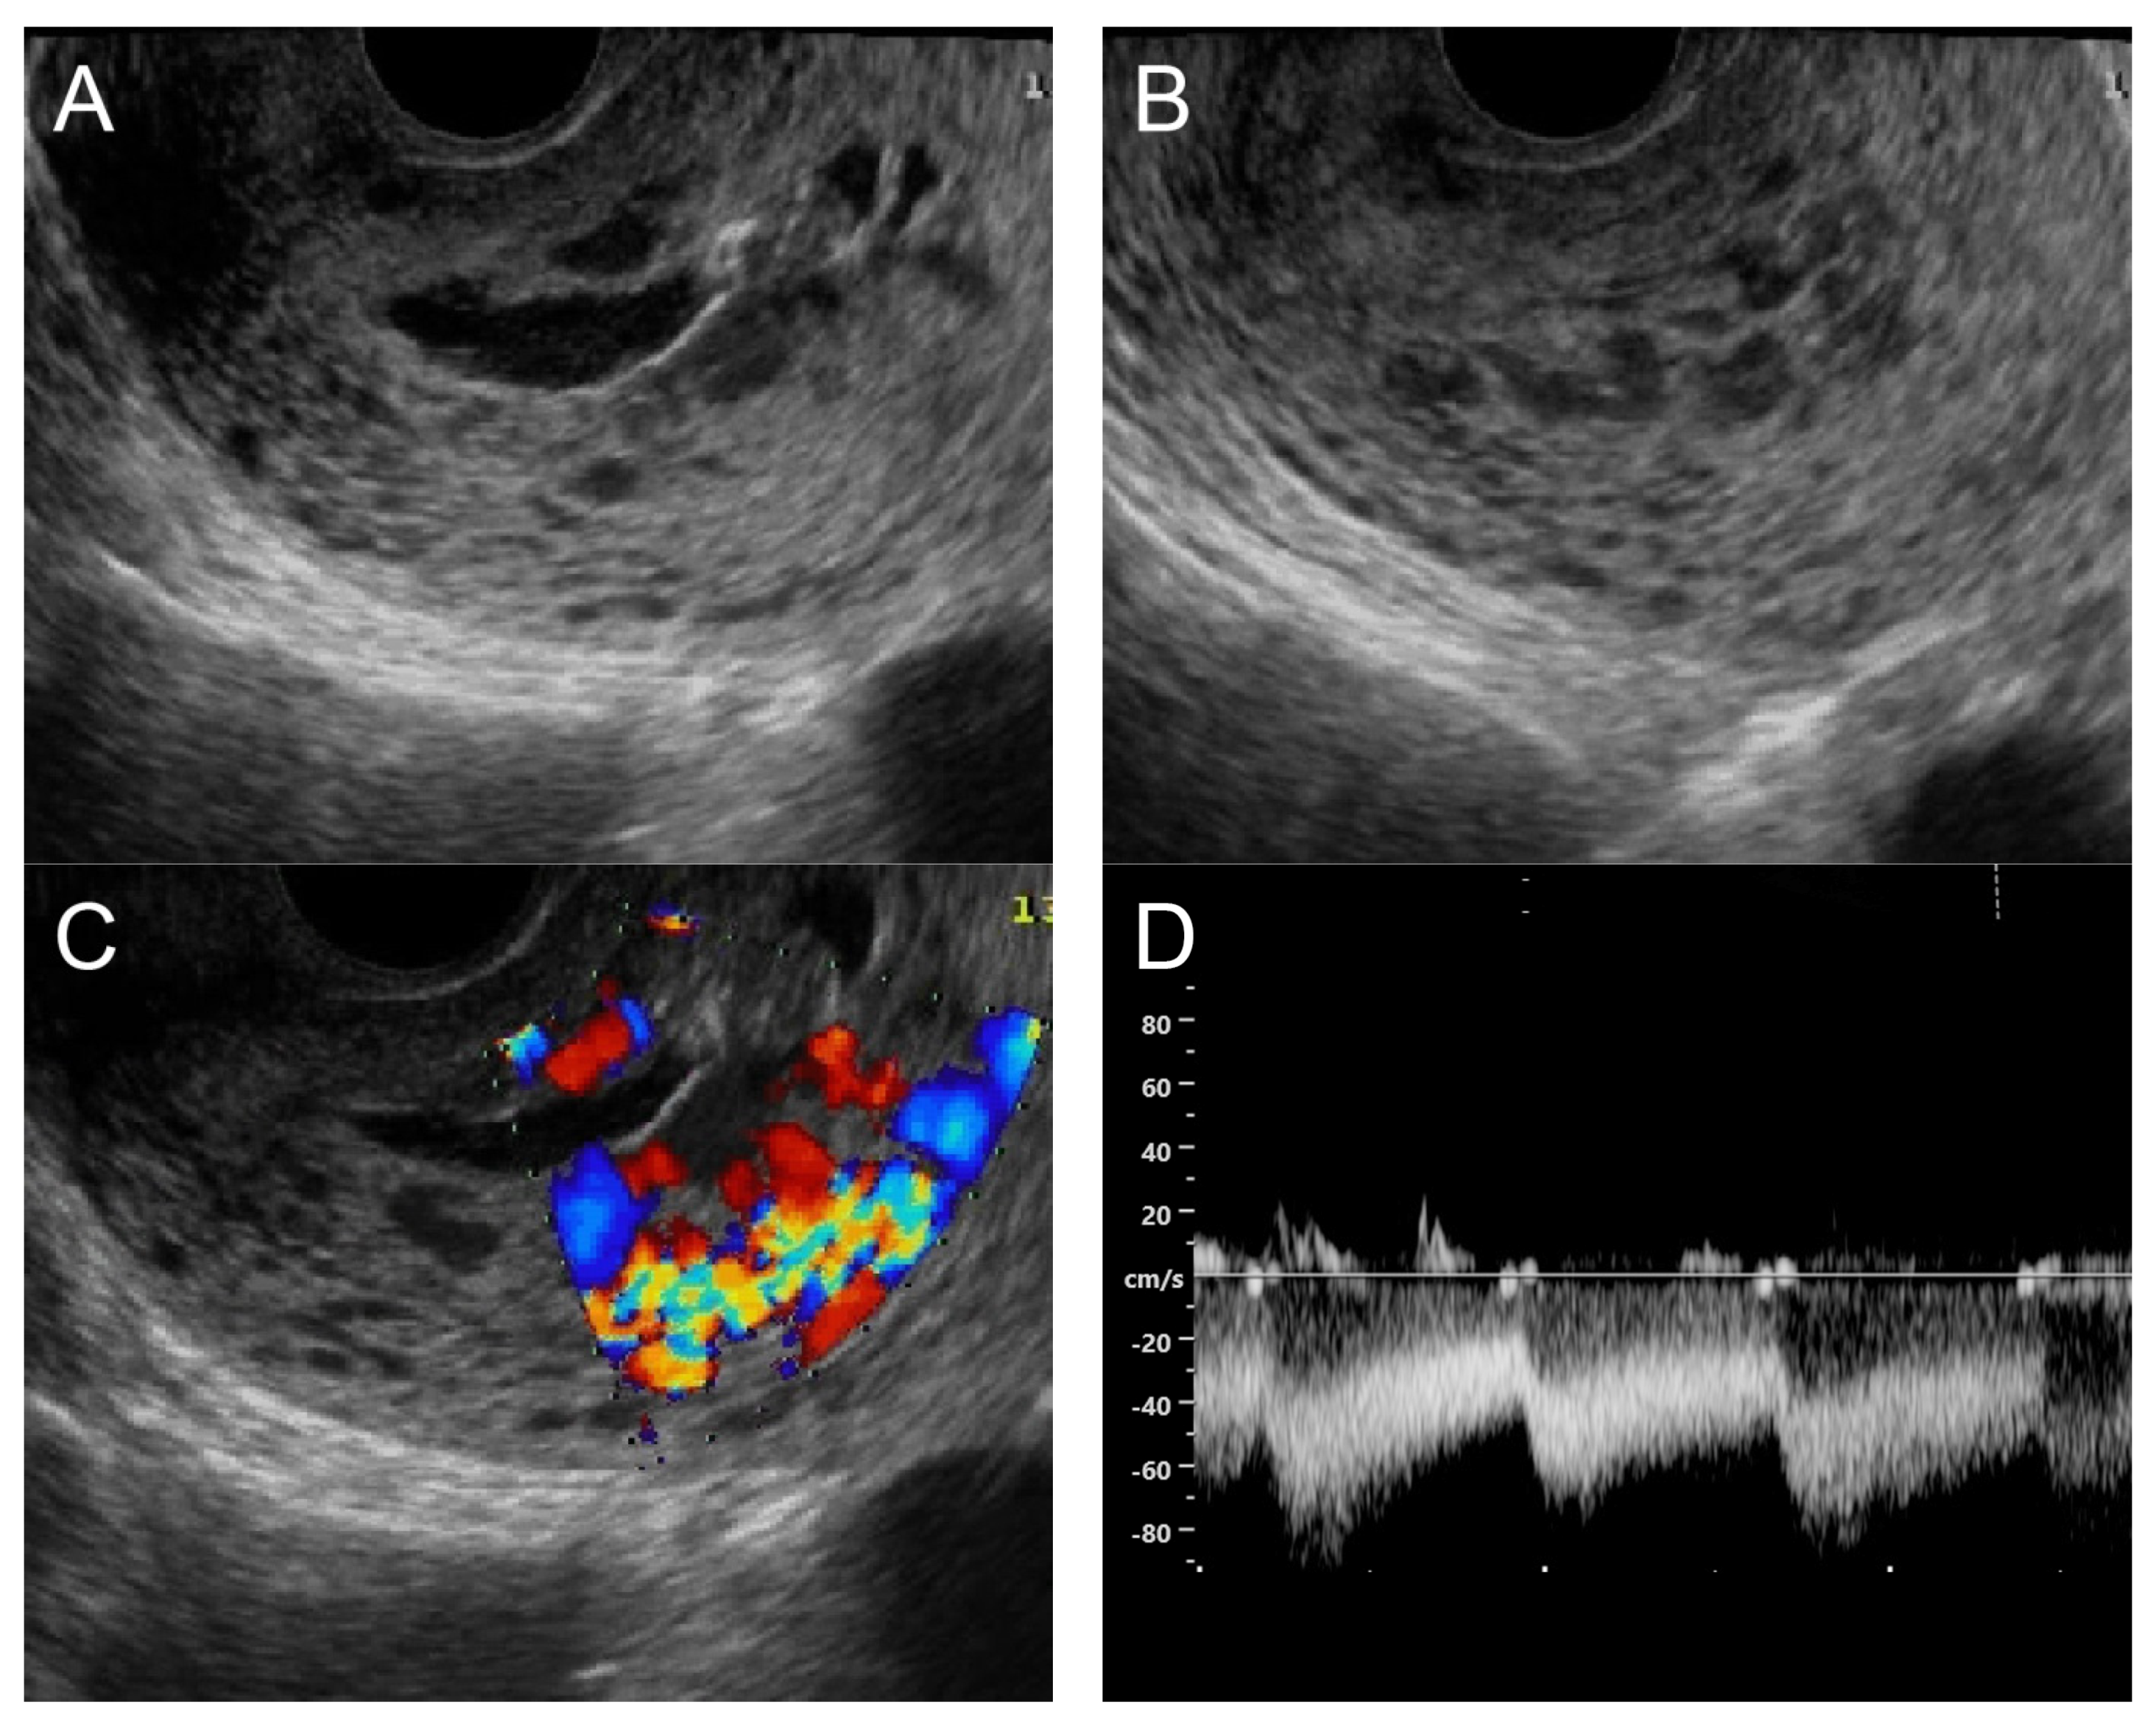

(A) Transvaginal ultrasound: sagittal scan of the uterus showed several dense small anechoic/hypoechoic tubular structures, mainly running to the endometrium, scattered throughout the anterior wall of the uterus; a thin endometrium; no other specific lesions of the uterus. There was anechoic fluid collection in the uterine cavity. (B) Cross-sectional scan of the fundus showed lesions with poorly defined outlines, containing several dense small anechoic/hypoechoic tubular structures, packed in the anterior wall. (C) Color flow mapping showed hyper-vascular areas in the myometrium, without well-defined lesion borders; multidirectional flow mainly localized at the anterior wall and the fundus. The main differential diagnosis was adenomyosis or gestational trophoblastic disease. (D) Spectral Doppler showed a high peak systolic velocity (~50 cm/s) with a low resistance index of 0.3. Note that in differentiating from adenomyosis, which sometime shows multiple minute anechoic or spongy-like areas but not lacunar lakes or tortuous vessels, adenomyosis is characterized by the absence of flow or minimal flow or by the presence of straight, scattered vessels traversing a hypertrophic myometrium [18,19], typically not containing a high flow peak systolic velocity, as seen in AMV, as mentioned earlier.